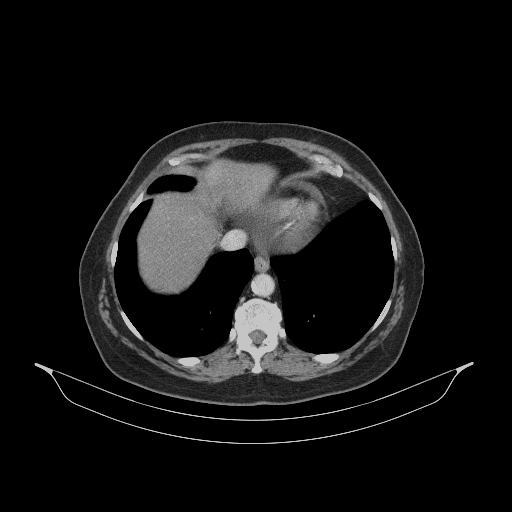

Original VENOUS CT scan

Full window (WL 1023.5, WW 4095 β†’ Low βˆ’1024, High +3071)

Lung window (WL -600, WW 1500 β†’ Low βˆ’1350, High +150)

Mediastinum window (WL 40, WW 400 β†’ Low βˆ’160, High +240)